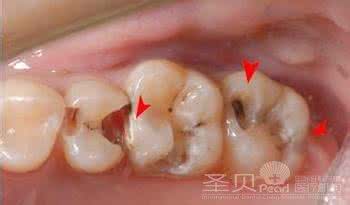

深龋:牙科出现明显蛀洞,产生剧痛。牙髓有机会受细菌感染而坏死,细菌甚至会从牙髓经牙根部分扩散至附近的牙周组织,引致发炎或脓肿。

治疗方法:牙髓治疗,如有需要,会镶配人造牙冠,如果牙科医生认为不适合进行牙髓治疗便需要脱牙。